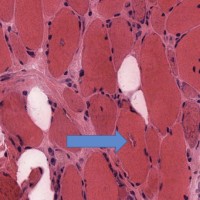

- Muscle biopsy shows endomysial and perivascular monocytic inflammation and necrosis with regeneration.

- Muscle biopsy shows perifascicular inflammation and atrophy with sparing of the central fascicle.